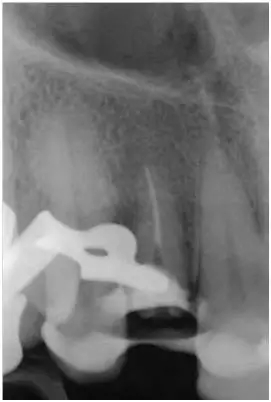

圖5:外傷9天后的影像學(xué)檢查:12牙牙冠在釉牙骨質(zhì)界水平處折斷并且可以看到根管充填和一個折斷的鈦根樁。所有牙齒均顯示輕度的水平向骨吸收,根尖周未發(fā)現(xiàn)異常。11至22牙牙冠被修復(fù)過。

圖10:12牙的影像學(xué)檢查:完全去除鈦根樁并暴露牙膠。